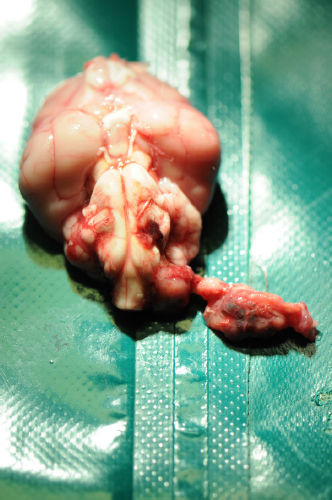

The necropsy revealed the presence of a voluminous dark red irregular mass which from the tympanic bulla invaded the posterior cranial fossa following the left glossopharyngeal nerve through the jugular foramen and the tympanic-occipital fissure (Fig. 2).

Fig. 2. A voluminous dark red irregular mass following the left glossopharyngeal nerve through the jugular foramen and the tympanic-occipital fissure.